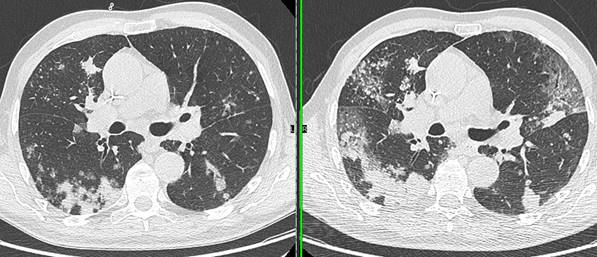

Les anomalies vues au scanner peuvent être classées en grade de sévérité débutant, avancé ou sévère. Les anomalies scanners sont bien corrélées avec la sévérité de l’atteinte clinique, ce qui est intéressant pour adapter la prise en charge.

Figure 3 : apparition de plages de verre dépoli bilatérales avec un aspect de pneumopathie (condensation) à droite, sur le scanner de mars, alors que le patient était suivi pour des lésions secondaires pulmonaires visibles en janvier 2020 ; patient de 76 ans, altération de l’état général. Le suivi évolutif est utile pour différencier ces nouvelles lésions très évocatrices d’infection Covid-19. Le diagnostic de Covid-19 a été confirmé après le scanner.

Figure 4 - reconstruction scanner 3d volumique qui met bien en évidence les zones lésionnelles (mars 2020)